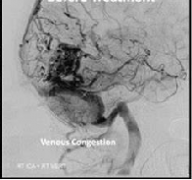

动静脉畸形(AVM),可以说是较复杂和较危险的脑血管病变,我们将考虑。Spetzler-Martin分级系统较初被认为是一种外科风险评估工具,它为AVM大小、位置和静脉引流模式分配分数,通常用于...

动静脉畸形 是绕过毛细血管系统的动脉和静脉之间的异常连接。这种血管异常因在中枢神经系统(通常是大脑AVM)中发生而广为人知,但可以出现在任何位置。尽管许多AVM无症状,但它...

脑动静脉畸形 (AVMs)是一种少见的脑血管病变,其特征是大量异常扩张的动静脉和直接动静脉分流。它们通常在青年期发现,并可伴有头痛、癫痫,或较常见的颅内出血,后者可导致...